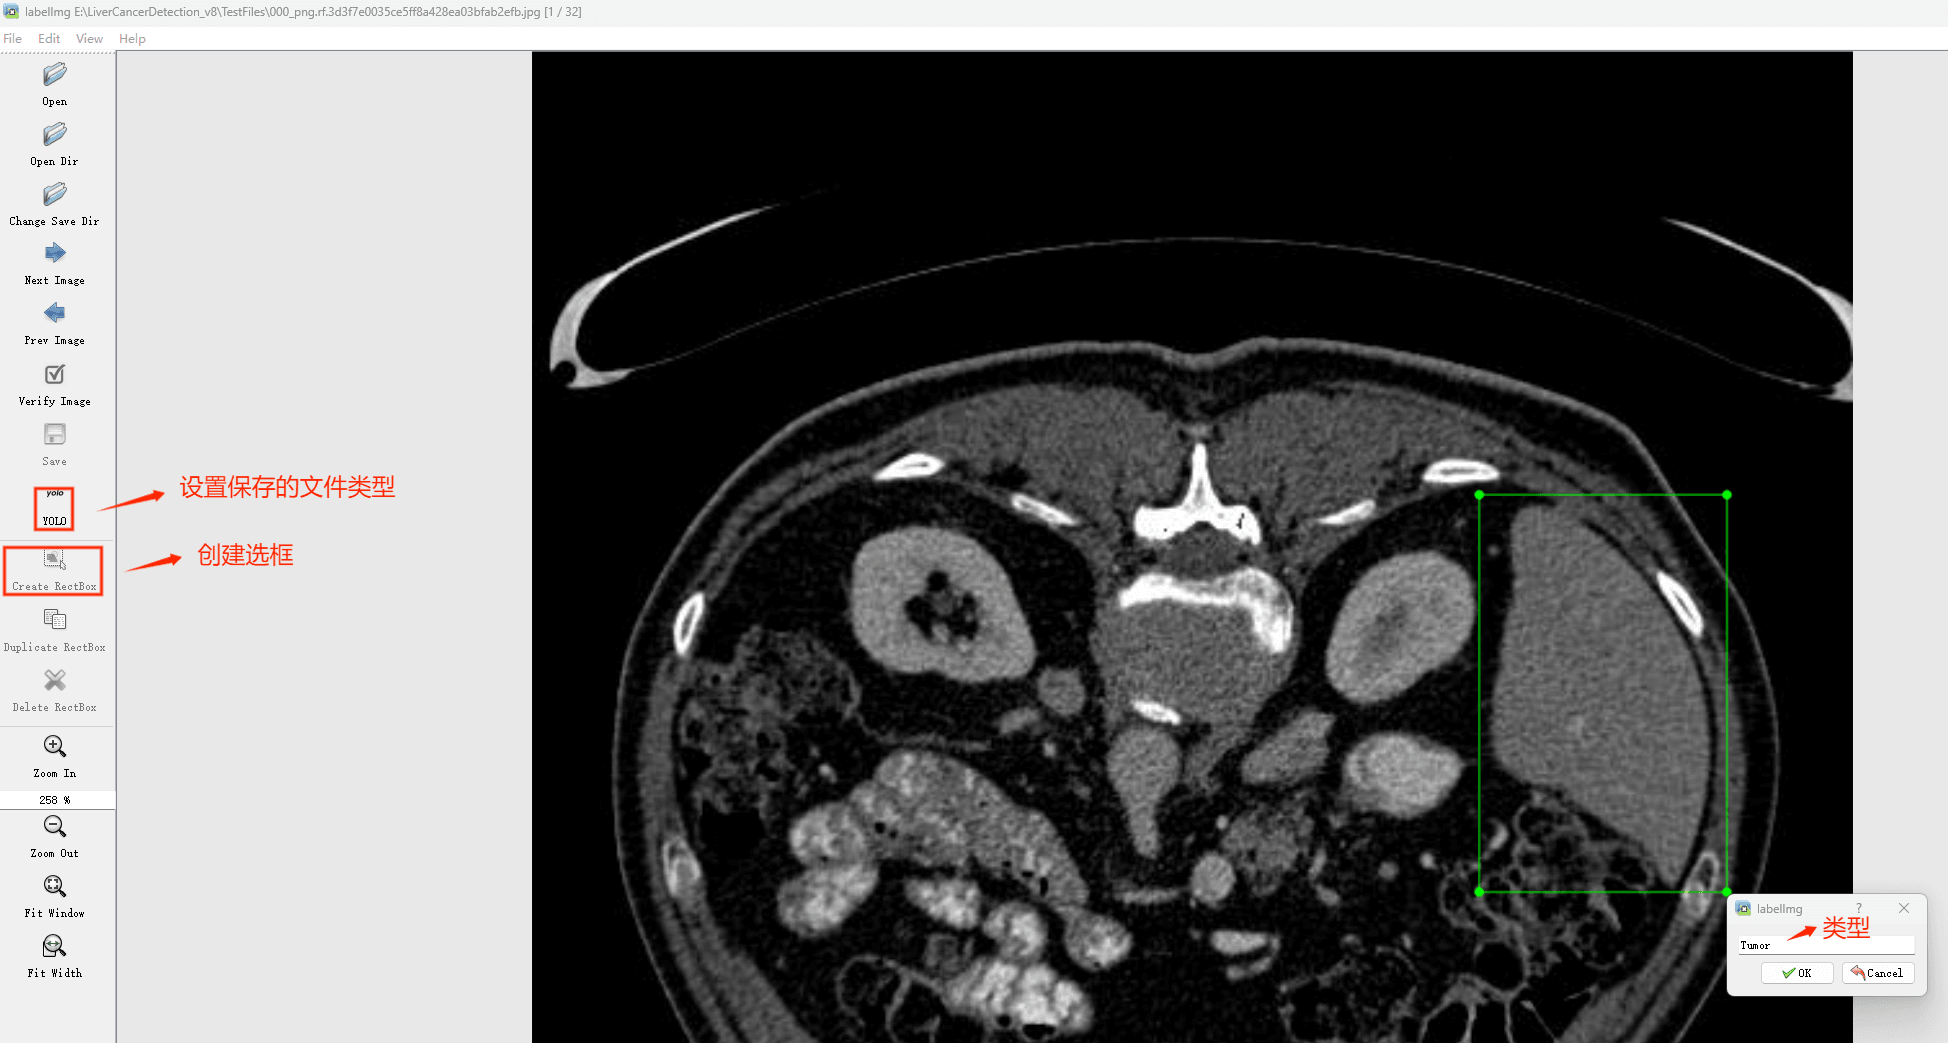

接下来就开始标注,画框,标记目标的label,然后d切换到下一张继续标注,不断重复重复。

(4)YOLO模式创建标签的样式

存放标签信息的文件的文件名为与图片名相同,内容由N行5列数据组成。

每一行代表标注的一个目标,通常包括五个数据,从左到右依次为:类别id、x_center、y_center、width、height。

其中:

–x类别id代表标注目标的类别;

–x_center和y_center代表标注框的相对中心坐标;

–xwidth和height代表标注框的相对宽和高。

注意:这里的中心点坐标、宽和高都是相对数据!!!

存放标签类别的文件的文件名为classes.txt (固定不变),用于存放创建的标签类别。

完成后可进行后续的yolo训练方面的操作。

本研究使用了包含各肝脏病症相关图像的数据集,并通过Labelimg标注工具对每张图像中的目标边框(Bounding Box)及其类别进行标注。然后主要基于YOLOv8n这种模型进行模型的训练,训练完成后对模型在验证集上的表现进行全面的性能评估及对比分析。模型训练和评估流程基本一致,包括:数据集准备、模型训练、模型评估。本次标注的目标类别为肝脏病症,数据集中共计包含12800张图像,其中训练集占10171张,验证集占2629张。部分图像如下图所示:

部分标注如下图所示: